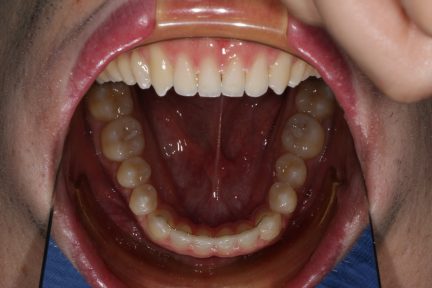

Classe III, articulé croisé antérieur, béance, espacement, diastème

État initial